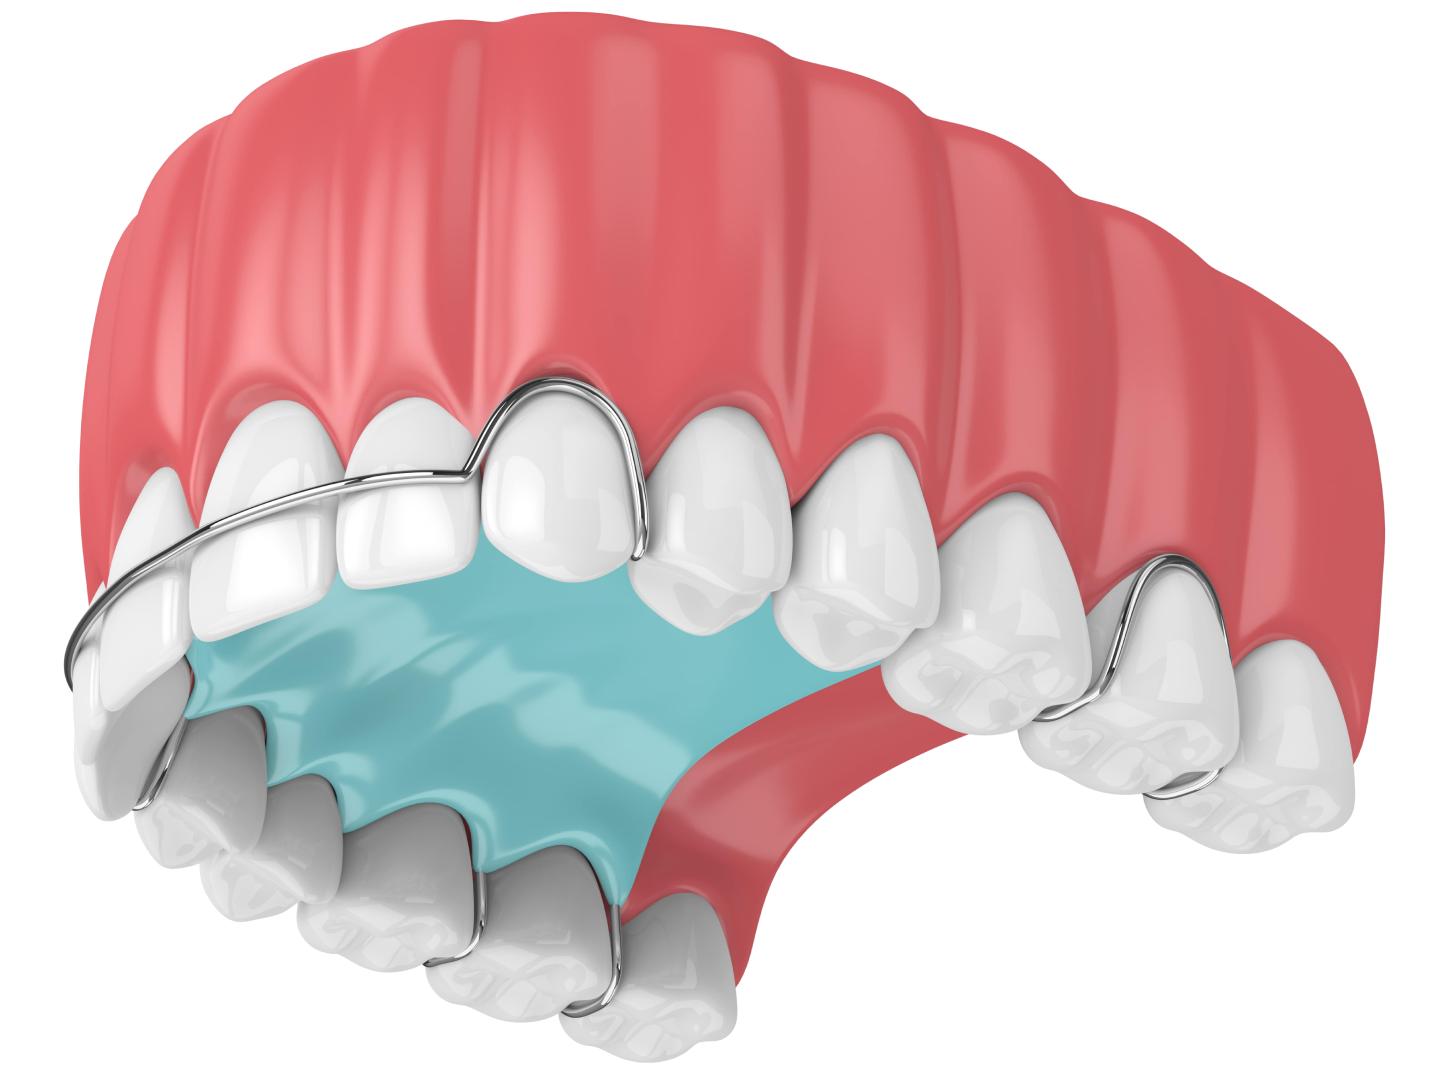

Ортодонтична пластина

Пластини для вирівнювання зубів — це знімна ортодонтична конструкція, яка складається з прозорої пластикової основи та металевої дуги. Виріб фіксується на піднебіння та зубні одиниці. Застосовується, щоб виправити кривизну зубів у дітей віком до 10 років, у яких щелепні кістки ще формуються. Дана система для не зміщує зубний ряд, а просто утримує його у необхідному положенні. Час носіння виробу залежить від серйозності патології та може становити 1,5–2 роки.

Переваги:

- доступна ціна;

- гіпоалергенні, нетоксичні та біосумісні з організмом дитини матеріали;

- простий догляд та гігієна ротової порожнини;

- безболісне вирівнювання зубів та відсутність дискомфорту при носінні;

- конструкцію можна знімати на час прийому їжі.

Недоліки:

- через те, що основа пластин встановлюється на піднебіння, може порушуватися дикція;

- потребує певного періоду адаптації;

- менш ефективний спосіб вирівнювання зубів порівняно з брекетами;

- підходять тільки для дітей.